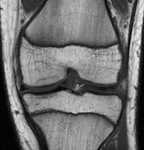

Preoperative anteroposterior magnetic resonance imaging (MRI)

From the collection of H. Chambers, MD